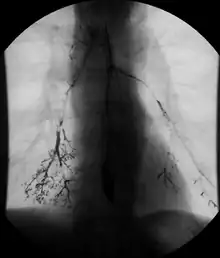

- Barium swallow X-ray examinations are used to study the pharynx[4] and esophagus.[2]

Barium swallow

Little or no preparations are required for the study of the larynx, pharynx, and esophagus when studied alone.[11] A thick barium mixture is swallowed in supine position and fluoroscopic images of the swallowing process are made. Then several swallows of a thin barium mixture are taken and the passage is recorded by fluoroscopy and standard radiographs. The procedure is repeated several times with the examination table tilted at various angles. A total of 350-450 mL of barium is swallowed during the process.[12][13] Normally, 90% of ingested fluid should have passed into the stomach after 15 seconds.[14]